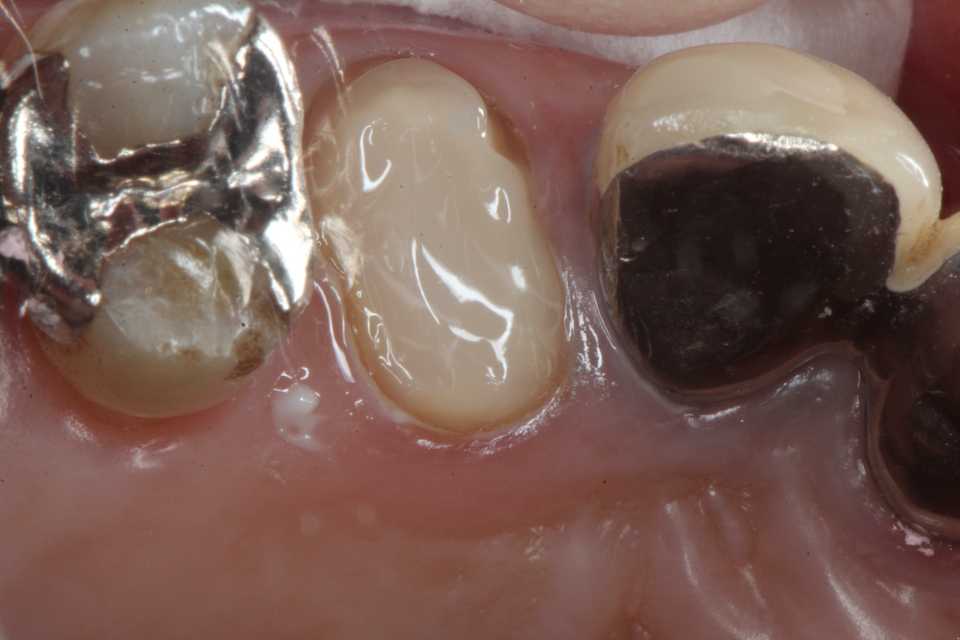

残根上のCR8 2025.10.28